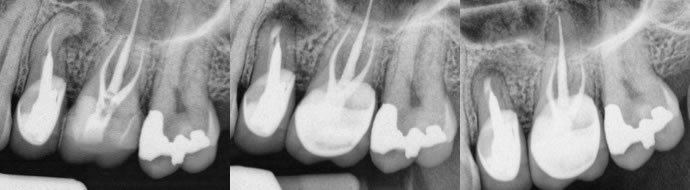

1. Thick or deeply set posts with well made coronal restorations. (figures 1-3)

Figures 1-3: pre-op / post-op / 9 months healing recall

Original root canal therapy performed by another endodontist and the crown was so perfect and the post deeply set. I performed the surgery on my friend with a great result.